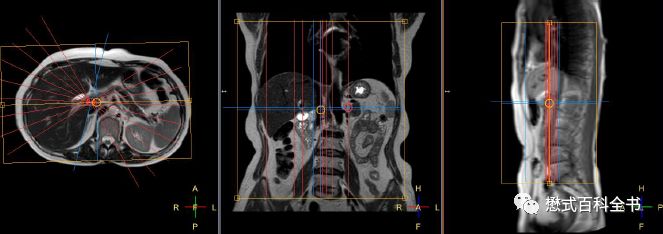

如果单独扫描MRCP,我们除了扫描定位像,首先需要扫描一个冠状位的T2WI好作为参考。最好再推荐扫描一个T2脂肪抑制的横轴位,这样MRCP的定位就更准确了。

定位的时候,在冠状位和横轴位上面一起定MRCP扫描的角度。

图17:MRCP的定位

关于在横轴位上定位的角度,MRCP有几种不同的打角度方法。

图18:MRCP扫描角度一

如上图所示,第一种扫描角度,是在3D冠状位扫描的时候,在横轴位上,扫描角度平行于主胰管走形。使用该定位角度显示胰管及胆总管下段可能比较好,但是对于肝内胆管,则由于角度问题,不能最好的反映左、右肝管汇合成肝总管的情况。

图19:MRCP扫描角度二

如上图所示,第二种扫描角度,是在3D冠状位扫描的时候,在横轴位上,扫描角度平行于左、右肝内胆管走形。使用该定位角度显示左、右肝内胆管及肝总管比较好,而且大家注意,使用这种角度,配合合适的FOV和扫描层数可以躲避到腹主动脉。而使用第一种定位角度,一般是无法躲避腹主动脉的。